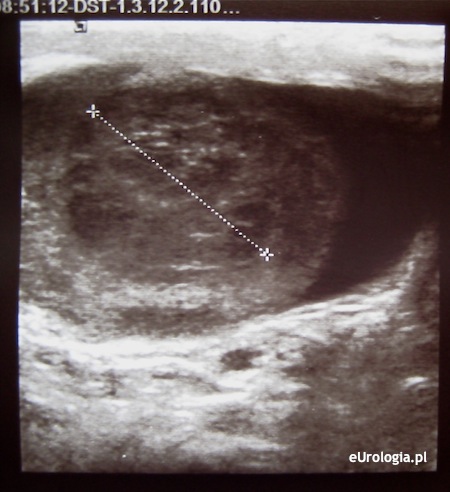

Fot. Guz jądra - obraz ultrasonograficzny jądra lewego z guzem.

Jednostronne powiększenie moszny z wyczuwalną twardą zawartością jest jednym z najbardziej niepokojących objawów w urologii. Bez badania USG odpowiedź na Pana pytanie jest niemożliwa. Przyczyną powiększenia moszny w opisywanym przypadku może być guz jądra lub wodniak. Badanie USG moszny da odpowiedź jaka jest przyczyna powiększenia moszny. Proszę pilnie skontaktować się z jakimkolwiek lekarzem w Pana okolicy w celu wykonania takiego badania. Wodniak jądra jest zmianą łagodną i nie wymaga pilnej interwencji. Wykluczenie lub potwierdzenie guza jądra ma dla Pana kluczowe znaczenie. Więcej informacji można znaleźć w dziale: USG moszny. W razie problemów ze znalezieniem lekarza w Belgii prosimy o kontakt z redakcją.